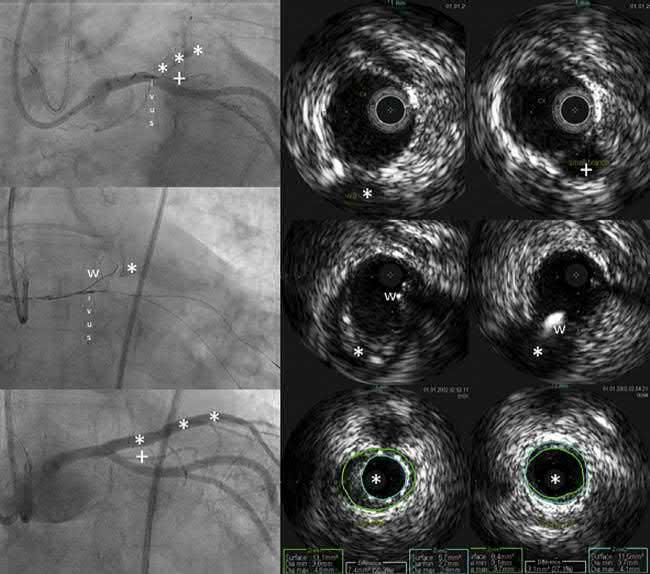

Asillustratedin Fig.5,IVUScanalsobeusedto resolveproximalcapambiguityandguidethepuncture ofstumplesslesionsbyimagingthroughasidebranch adjacenttotheocclusion.Ingeneral,afterlesioncrossing,IVUSwillconfirmthepresenceofthewireinthe distaltruelumen.Itmightalsobehelpfultonavigate theguidewirebackinthetruelumenincaseofadissectionandsubintimaltracking,usingtheIVUScatheterinthesubintimalspacetoguideantegradereentry inthetruelumen.Thishighlycomplexmethodisonly recommendedasalaststepinthelatestalgorithmproposedtotreatCTO,131 recommendingcarefulselection foraretrogradestrategyinwhichIVUSisalsoveryuseful.Thepreferredretrograderecanalizationstrategyis basedonthe(reverse)controlledantegradeandretrogradesubintimaltracking(CART)techniqueforwire reentryinthetrueproximallumen.IVUScanshow (i)therespectivepositionoftheantegradeandretrogradewireintraplaqueorinthesubintimalspace, (ii)thesizeofthevesselforoptimalballoonselection fortheCART,and(iii)thebestlocationformakingthe connectionofthewires.132,133

FIG.5 IVUSperformedduringaCTOPCIprocedure.Atotallyoccludedleftanteriordescending(LAD)arteryat theleveloftheostiumispointedontheangiogramonthe topleft by *** Topright,onthecorrespondingIVUS crosssectionobtainedjustdistallytotheoriginoftheLAD,withthecatheterintheleftcircumflexartery(Cx),a smallsidebranchismarkedby+,alsovisibleontheangiogram.TheIVUScrosssectioninthemiddlejustmore proximallyshowstheoriginoftheLAD(*). Middlepanel,left,showstheangiogramduringthefunctionofthe proximalcapoftheLADwithawire(w)thatcanalsobefollowedontheIVUSimagesinrealtime.The lowerpanel showsthestentedLADandtheIVUSassessmentofstentexpansionintheLAD (middlepanel) anditsdistal reference.